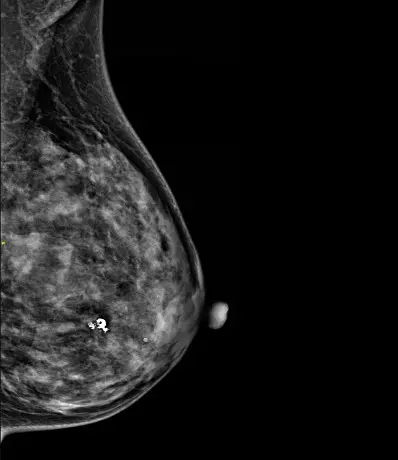

在钼靶的报告单上,钙化应该是最常见的描述性语言。钼靶片子就像一张乳房的黑白照片,钙化就是看到的乳腺里白色的小点(见图1,2),不要见到钙化就以为是恶性的,其实多数钙化还是良性的。

(图2,钼靶上的恶性钙化)

根据钙化的形态和分布特征可以分为良性和恶性钙化,如散在的点状钙化,孤立的,粗大的,圆圆的钙化是良性的,而集群样,针尖,多形性的钙化有可能是恶性的。